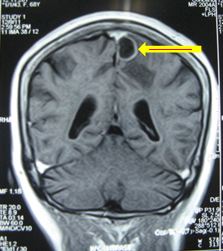

Chụp MRI sọ não (12/12/2011):

Hình 2: Hình ảnh chụp MRI sọ não có khối u não vùng đỉnh trái, 20×19mm, ngấm thuốc quanh u